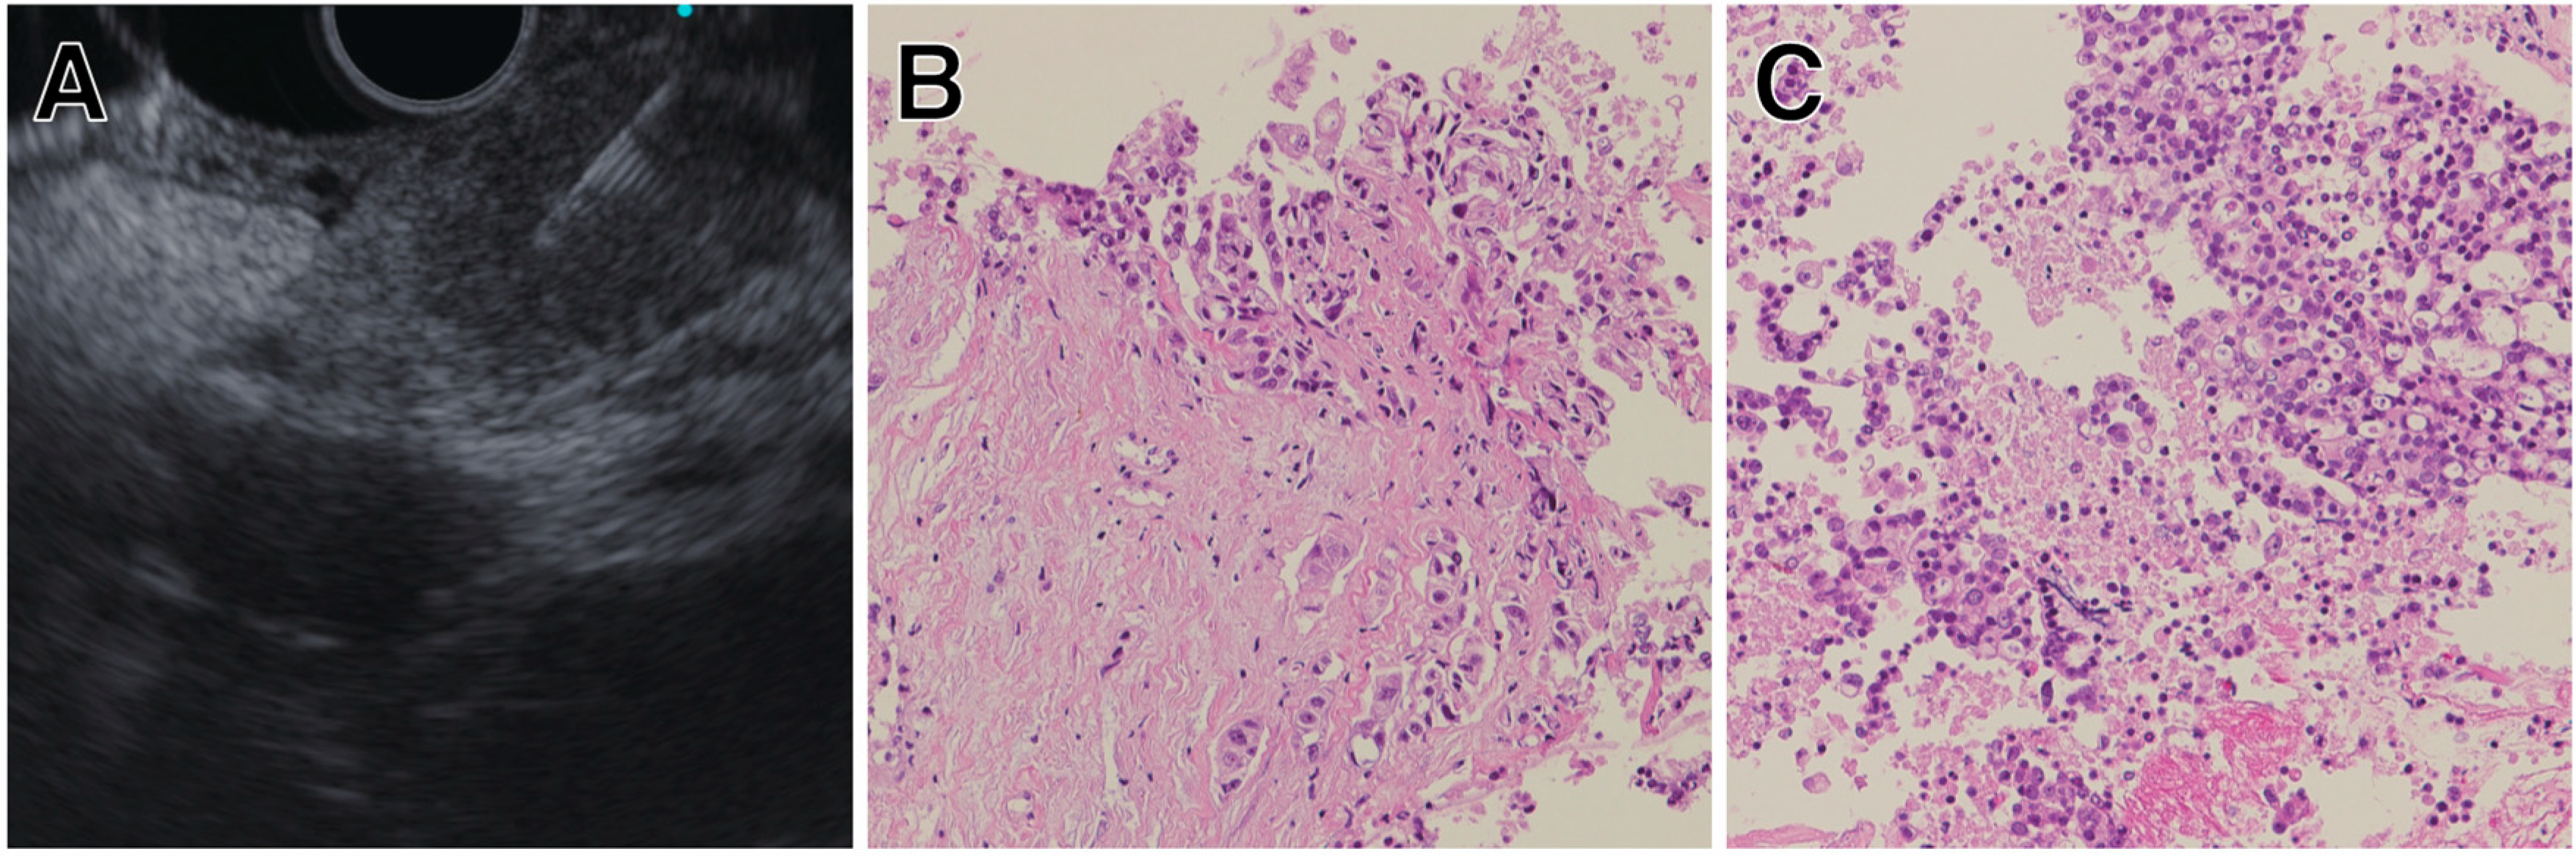

- Oh, D.; Seo, D.W.; Hong, S.M.; Jun, J.H.; Song, T.J.; Park, D.H.; Son, B.K.; Lee, S.S.; Lee, S.K.; Kim, M.H. The usefulness of contrast-enhanced harmonic EUS-guided fine-needle aspiration for evaluation of hepatic lesions (with video). Gastrointest. Endosc. 2018, 88, 495–501. [Google Scholar] [CrossRef]